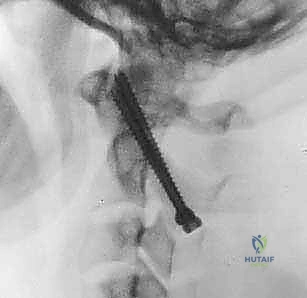

الخطوة 7: التصوير الشعاعي داخل العمليات

طوال الإجراء، وخاصة بعد تركيب المسامير والقضبان، يتم استخدام جهاز الأشعة السينية المحمول (C-arm

تُعرف التقنية الأكثر شيوعاً وفعالية اليوم باسم تقنية هارمز/جويل (Harms/Goel Technique)، والتي تتضمن وضع مسامير في الكتل المفصلية للفقرة C1 ومسامير في عنيقة أو جزء (Pars) الفقرة C2، ثم ربطها بقضبان معدنية. يتطلب هذا الإجراء مهارة جراحية فائقة، استخدام الميكروسكوب الجراحي، والتوجيه بالأشعة السينية داخل غرفة العمليات.

بعد وضع المسامير الأربعة بنجاح، يتم تقييم وضعية الفقرات. إذا كانت C1 منزلقة للأمام، يتم استخدام أدوات خاصة لسحبها للخلف واستعادة المحاذاة الطبيعية مع C2 (عملية تُسمى Reduction). بمجرد تحقيق الوضعية المثالية، يتم قص قضيبين من التيتانيوم بالطول المناسب وتثبيتهما بقوة في رؤوس المسامير. هذا يخلق "سقالة" معدنية صلبة تمنع أي حركة بين الفقرتين.